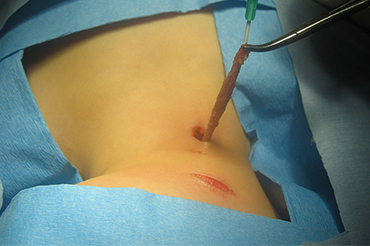

Fistula Branquial